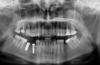

Elena_R Опубликовано 23 апреля, 2008 Поделиться Опубликовано 23 апреля, 2008 спасибо, завтра снимок захвачу. снимок Ссылка на комментарий

Bier Опубликовано 24 апреля, 2008 Поделиться Опубликовано 24 апреля, 2008 все отличненько у вас стоит. Ссылка на комментарий

Doc Опубликовано 24 апреля, 2008 Поделиться Опубликовано 24 апреля, 2008 снимок Очень хорошо. Ссылка на комментарий